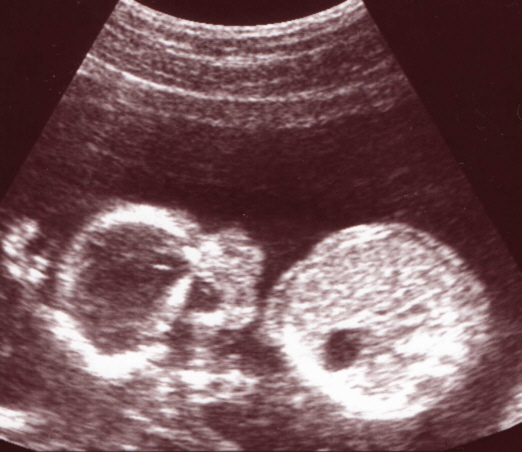

16 Wochen und 6 Tage

Ivo ist inzwischen stolze 10 cm groß.

Links sieht man das Köpfchen und rechts den Rumpf. Der schwarze Punkt mitten im Rumpf ist der Magen.